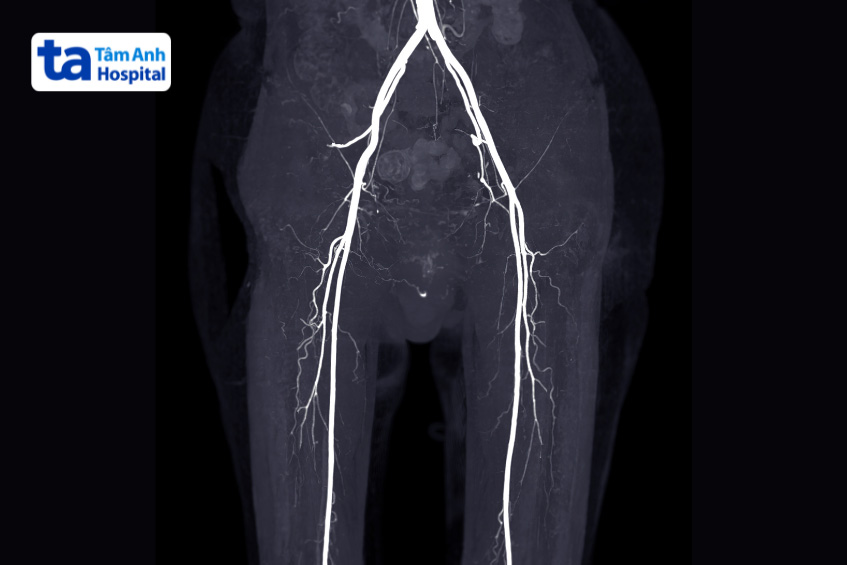

Để chẩn đoán bệnh động mạch chi dưới, người bệnh có thể được chỉ định thực hiện một số phương pháp sau:

Trong phương pháp chụp CT, công nghệ tia X được sử dụng để chụp nhiều hình ảnh của cấu trúc bên trong cơ thể. Trước khi chụp, bệnh nhân có thể được tiêm một liều chất phản quang thông qua tĩnh mạch. Chất lỏng này đi qua các mạch máu và làm nổi bật các tắc nghẽn trong các động mạch chân. (4)

Đây là phương pháp phổ biến giúp chẩn đoán bệnh động mạch ngoại biên. Phương pháp mang đến hình ảnh chính xác, khách quan nhất và có giá trị nhất trong quyết định chẩn đoán và điều trị.